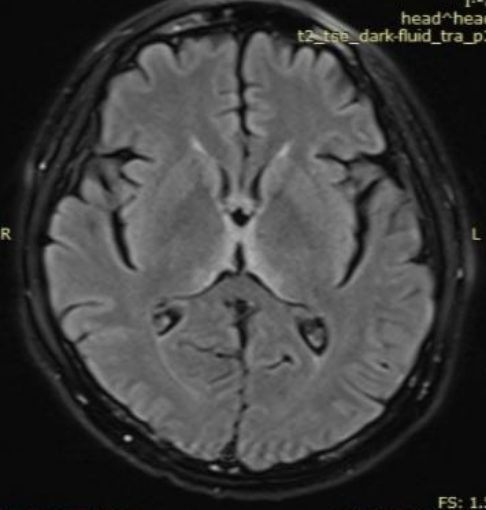

61岁男患,癫痫。2014年头MRI如下:

2020年头MRI如下:

答案:脑淀粉样血管病相关炎症(CAA-RI)。多呈急性或亚急性起病,最常见的表现是认知及行为改变,可表现为不同程度的痴呆、幻觉、人格改变、意识障碍甚至昏迷,其次是偏瘫、偏身感觉障碍、失语、共济失调等局灶性神经功能受损表现。另外,以癫痫、头痛等症状起病的患者亦不在少数,而相比单纯CAA而言,颅内出血的发生率则较低。MRI上最常见的表现为软脑膜明显强化及T2WI或FLAIR上的皮质下白质高信号灶,病灶常为非对称性,可散在分布或融合成片,灰质较少累及。